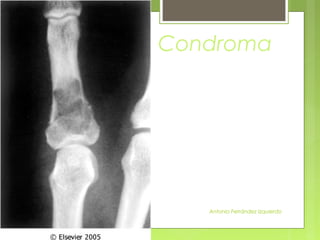

• Tumores de cartílago más frecuentes y se

suelen diagnosticar entre los 20-50 años.

• Pueden originarse en la cavidad medular

(encondromas) o en la superficie del hueso

(condromas subperiósticos o

yuxtacorticales).

• Los encondromas pueden ser solitarios o

múltiples.

Condroma

- Los solitarios se localizan en la región

metafisaria de los huesos cilíndricos,

sobre todo en manos y pies.

- Los múltiples (encondromatosis) se

conocen como enfermedad de Ollier

o síndrome de Maffucci (si se asocia a

angiomas de partes blandas).